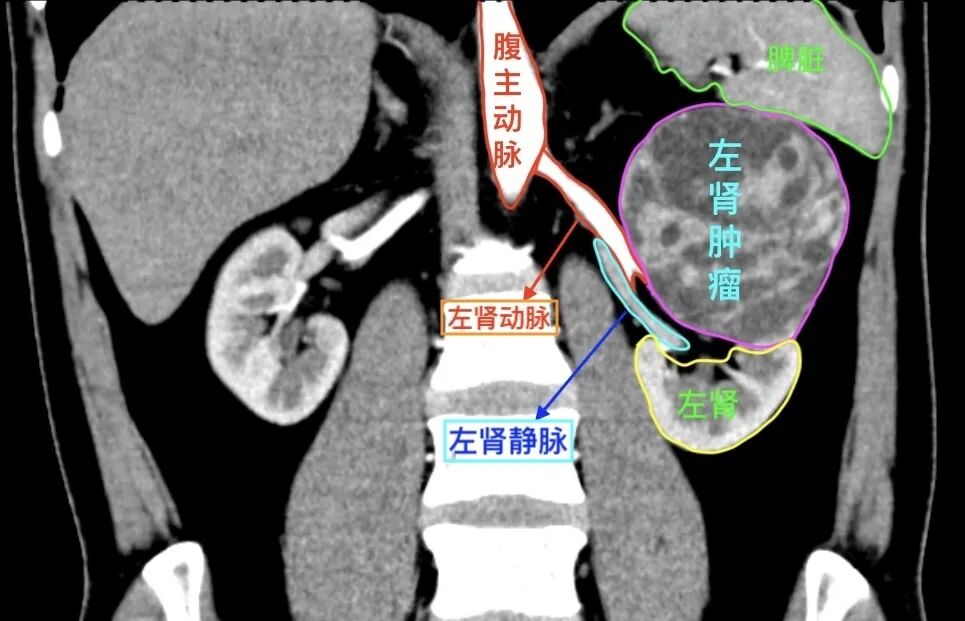

患者文先生在一次常规体检中,意外发现左肾存在一个巨大占位。进一步的增强CT检查结果令人倒吸一口凉气:一个大小约93×82×90mm的类圆形肿瘤从肾脏突出,位置极其凶险,紧贴着肾门部的大血管和集合系统。经专业评估,该肿瘤R.E.N.A.L评分高达11分,属于“高度复杂”级别。